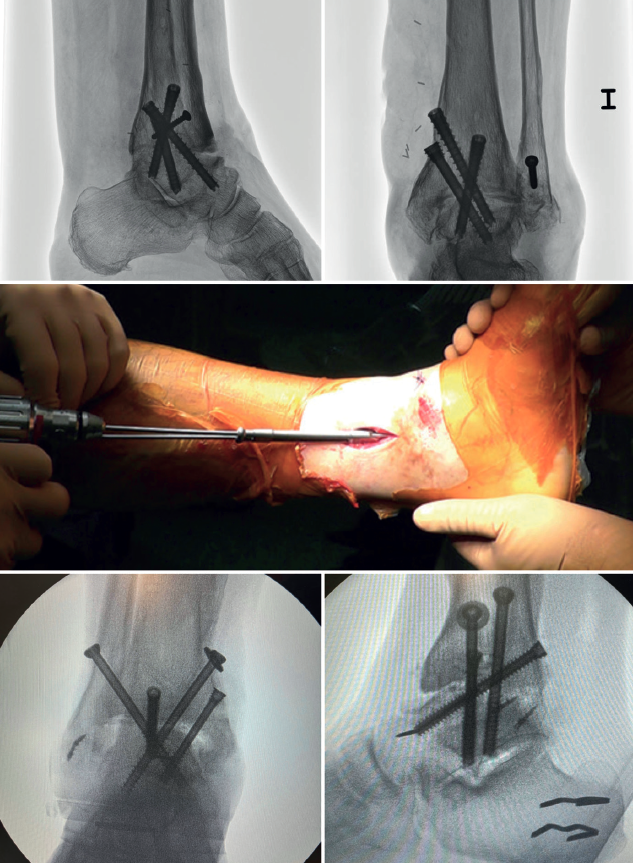

En las artrodesis de tobillo por vía artroscópica, el uso de tornillos a compresión colocados de forma percutánea es la técnica de elección (Figura 5).

La mayoría de los autores consideran el uso de tornillos canulados (de 3 a 4) como el método idóneo de fijación. Los diámetros de los tornillos escogidos oscilarán entre los 6 y los 7 mm. Con esta técnica se consigue del 85 al 100% de fusión y entre el 84 y el 95% de satisfacción del paciente(19).

Van Dijk, Kerkhoffs et al.(20) reportan excelentes resultados con el uso de 3 tornillos como método estandarizado para las artrodesis de tobillo.

Configuración y colocación de los tornillos

Dependiendo de la deformidad y en función de la planificación preoperatoria, se realiza la colocación de los tornillos, comenzando con el tornillo de compresión que contrarresta la deformidad.

Es decir, en las artropatías con componente de varo empezaríamos por un tornillo lateral, mientras que en las desalineaciones en valgo la recomendación es colocar el primer tornillo desde medial. El segundo tornillo debería ser del lado opuesto al primero. Ambos deben realizar la compresión adecuada entre superficies articulares(17).

En general, se utilizan un mínimo de 3 tornillos. El tercer tornillo es el denominado home run, cuya importancia destacan en su trabajo Holt et al.(21). Se dirige cruzando el tobillo desde la parte posterior de la tibia hasta el cuello del astrágalo. Puede utilizarse un cuarto tornillo a modo de aumentación del primero, del que contrarresta la deformidad principal.

Goetzmann et al.(22), en su serie de revisión de 111 casos, respaldan el uso de al menos 3 tornillos para la fijación de la artrodesis tibioastragalina artroscópica. Añadir un tercer tornillo parece asociarse con un menor riesgo de pseudoartrosis y un menor tiempo de consolidación. Estos efectos pueden atribuirse a una mayor estabilidad del constructo.

Glick, Myerson(23) et al. publicaron que la configuración que conferiría mayor rigidez a la osteosíntesis es con 2 tornillos desde medial y 1 desde lateral.

En aquellos casos donde existe una traslación anterior de astrágalo, es importante una buena resección del maléolo posterior tibial para permitir su reducción y posicionar bien al astrágalo. Otra técnica útil es, en decúbito supino, colocar un soporte bajo la tibia distal dejando el talón libre para poder desplazarlo manualmente a posterior.

En algunos de estos casos con traslación anterior del talo, a diferencia de las recomendaciones habituales, puede ser útil posicionar primero el tornillo posteroanterior con rosca parcial, para reducir el astrágalo de anterior a posterior y alinearlo con el eje longitudinal lateral.

Se toman radiografías definitivas anteroposterior, de mortaja, lateral del tobillo, dorsoplantar y oblicua del pie para confirmar la correcta reducción, la posición y la longitud de los tornillos, en especial del tornillo home run (Tabla 3).